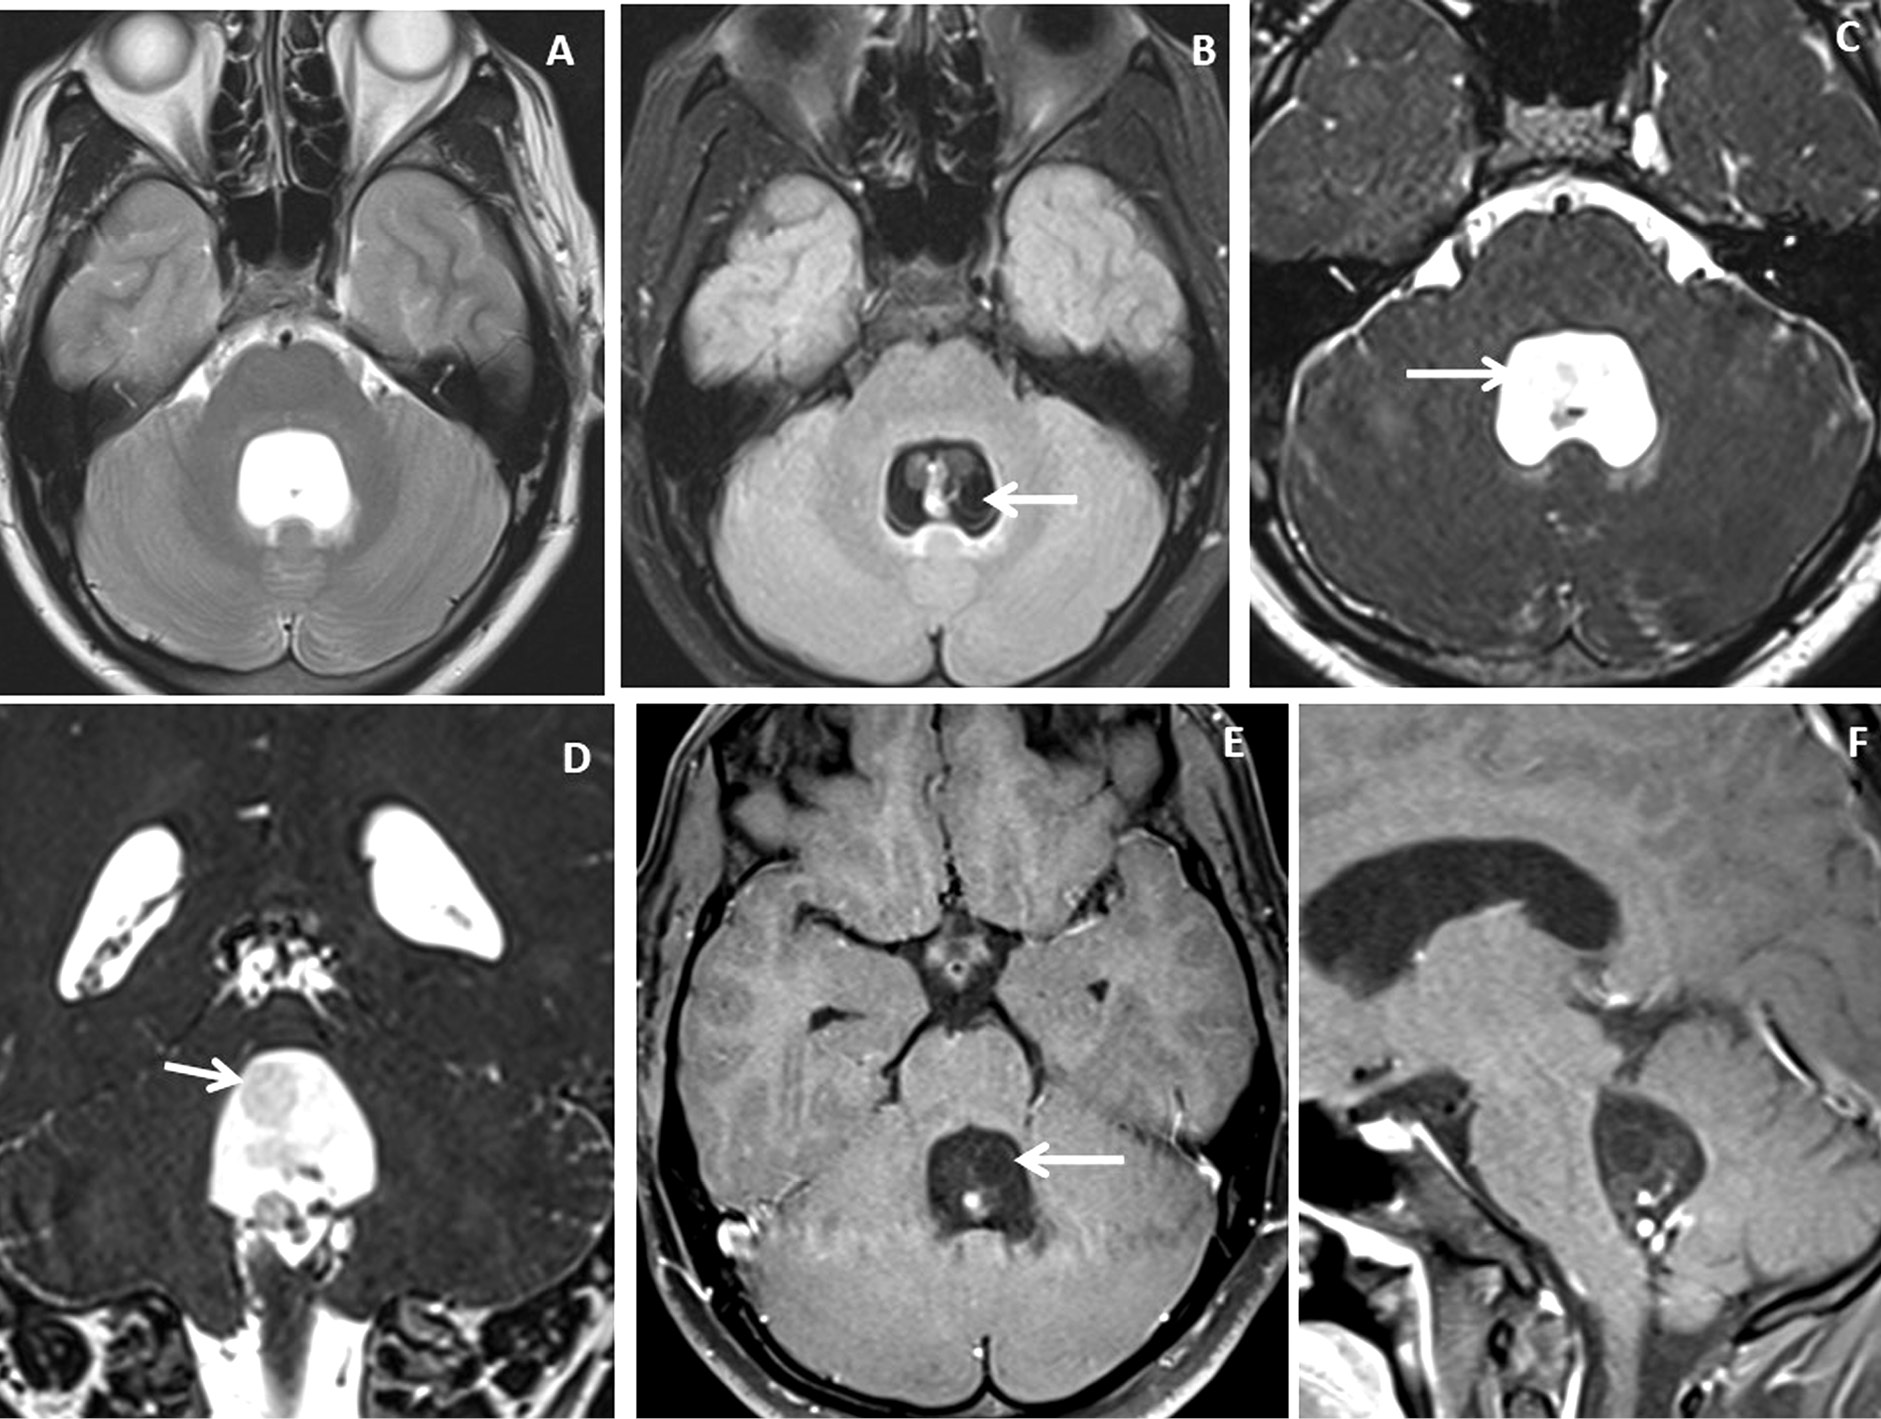

Figure 4. Brain magnetic resonance imaging of 13 years male with severe headache, vomiting and acute neurological deterioration. (A-B) Axial T2WI images show marked distension and dilatation of the fourth ventricle with marked periventricular CSF seepage and supratentorial hydrocephalus. (C) Axial FLAIR image shows cystic lesions within the fourth ventricle (arrow). (D-E) Axial heavily T2W images show thin-walled hyperintense cystic lesions within the 4th ventricle with an oval to elongated appearing cystic lesion with scolex in the right foramen of Luschka (arrow). (F-H) Axial and sagittal T1W post-contrast image shows a thin peripheral enhancing cystic lesion with an irregular mural nodule in the right foramen of Luschka (arrow) and thin smooth enhancement of the intraventricular cysts. Nodular enhancement was seen in midline inferior margin of 4th ventricle near to foramen of Magendie (arrow).

Very thin smooth cyst wall enhancement was observed in 9(90%) patients (Figure 1 and 2) and irregular peripheral rim-like wall enhancement with an irregular nodule in 1(10%) patient. Ventricular ependymitis with smooth to irregular ependymal lining enhancement was observed in 7(70%) patients (Figure 3). Presence of hydrocephalus detected in 8(80%), where MRI revealed asymmetrical enlargement of lateral ventricle with periventricular CSF seepage in 4(40%) patients (Figure 1), dilatation of 3rd ventricle in 2(20%) patients and ballooned 4th ventricle in another 2(20%) patients(Figure 4).

Four (40%) patients were treated conservatively with cysticidal drugs only and 6 (60%) patients were treated surgically followed by cysticidal drugs. Craniotomy with micro-surgical resection was done in 2 patients with 4th ventricular neurocysticercosis and endoscopic approach in another 4 patients with lateral and 3rd ventricular neurocysticercosis. On follow-up, 8(80%) patients show complete healing of the intraventricular neurocysticercosis, 1 (10%) patient showed disease recurrence and another 1 (10%) patient died.